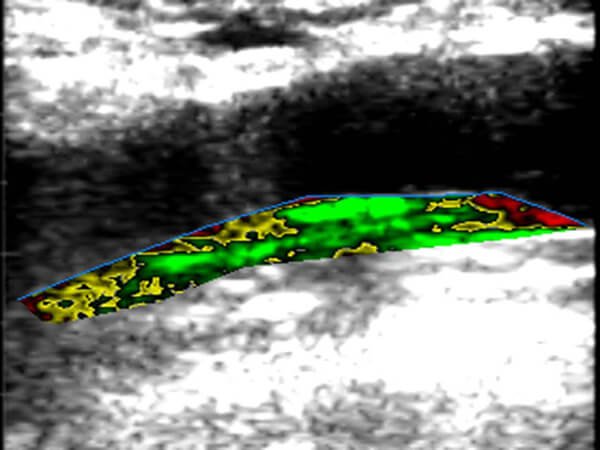

- Detección y estudio de placas de colesterol

- Caracterización de riesgo de placas ateroscleróticas (estables vs vulnerables)

- Diagnóstico de aterosclerosis subclínica